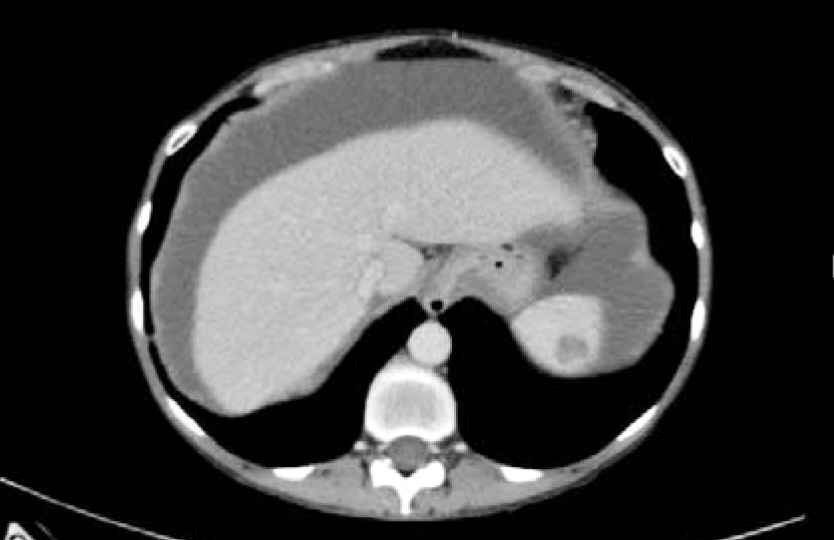

A 58-year-old female with no significant PMH, presented to the ER with acute onset abdominal pain, nausea, vomiting and diarrhea for one day. Patient was in her usual state of health eating and drinking normally, when she started having diffuse abdominal pain. Initially thought it was “gas pain”, but progressed to 9/10 pain throughout the day. Her pain was also accompanied by nausea, multiple episodes of vomiting and diarrhea. A CT abdomen pelvis revealed large bilateral pelvic masses obstructing the colon and ureters (Figure 6 and 7). Soft tissue nodules and ascites also present. Findings were most concerning for peritoneal carcinomatosis (Figure 8 and 9).

Figure 8: CT scan abdomen and pelvis. Multiple liver and splenic implants.

Figure 9: CT scan abdomen and pelvis. Peritoneal implants suggestive of carcinomatosis.